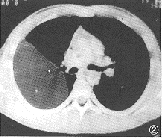

患者 男,17岁。体检发现右胸腔内巨大椭圆形肿物,边界清(图1)。

图1 CT定位片示右侧胸腔巨大椭圆形肿块,边界清